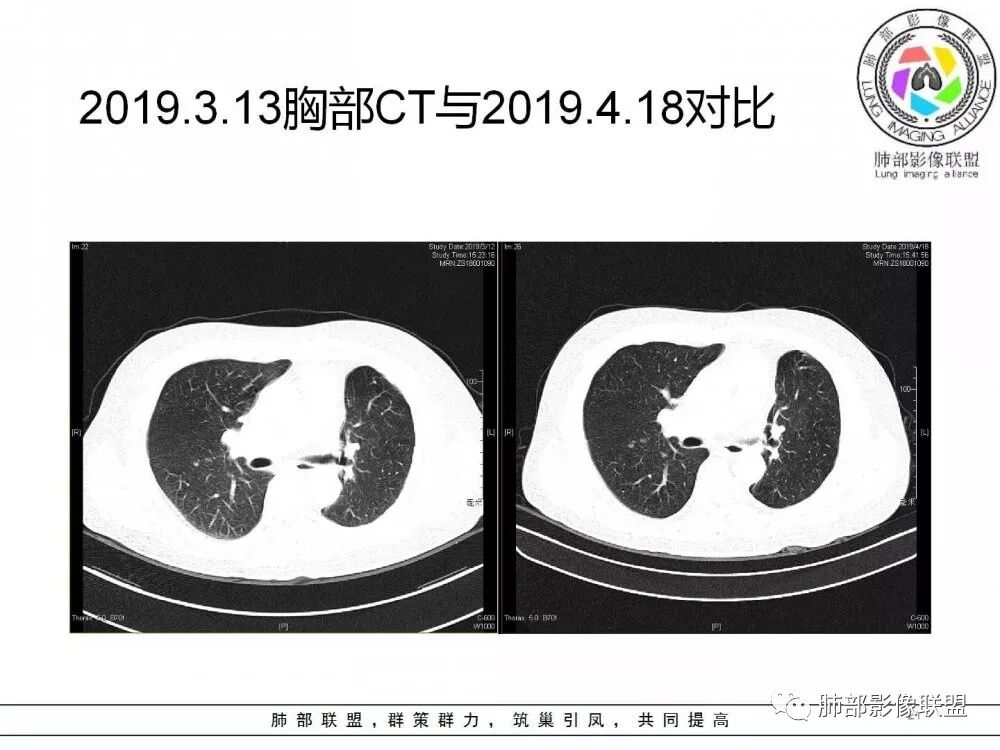

病灶从2月份就开始有,应该最早说是1月7号就有了,到3月13号稍微增大一点,到后面几乎没变化,到5月份好像稍微大一些,炎性应该是炎性,犹豫的是这个炎性到底什么病变呢?其实本没变化,它特点一个是在叶裂上,跟血管关系密切,但是病灶边缘稍收缩,病灶没有太大变化。

确实当时病人来了考虑转移可能,就测了基因,上了靶向药,两月变化不大

因为这个长轴似乎跟支气管走行一致的,其实治疗效果不是很理想,我先把性质定为炎性。因为这个病灶它沿着血管支气管走行的方向,大家都考虑隐球菌,这么久病灶无明显变化,它跟血管束关系很密切。我犹豫就在此,到底是IgG4还是隐球,大方向是炎性,不符合的就是也在激素治疗。